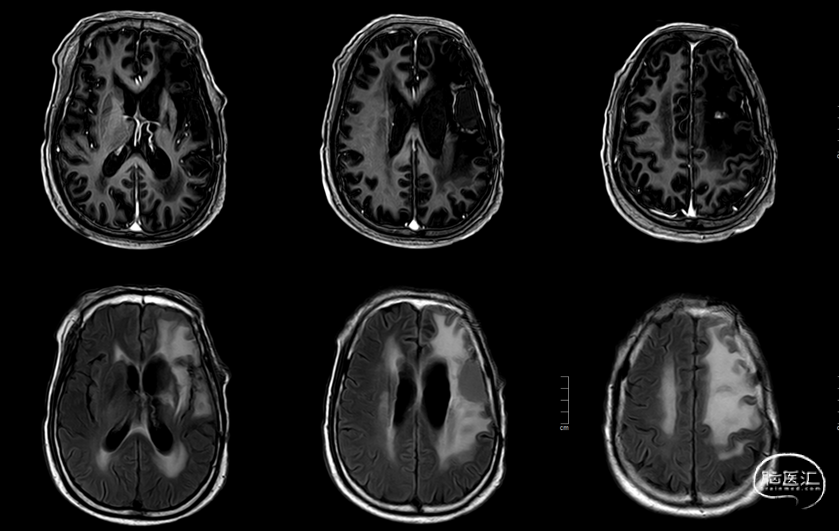

肿瘤电场治疗16天,RT后1月(2020-07-22):图示。

放疗后8月(2021-03-17):如视频和图像。

考虑无明显占位效应,病情评估SD,继续化疗+肿瘤电场治疗。

术后5周开始实施标准的新STUPP方案的辅助治疗,即在同步放化疗后,辅助替莫唑胺化疗的同时使用了电场治疗。目前生存25月,且临床和影像学表现均提示稳定,未见复发迹象。期间,在放疗后7月时复查MRI提示异常FLAIR信号区增大,经我院MDT讨论,考虑到强化信号减轻,无明显占位效应,患者无症状体征,考虑是治疗后水肿,非进展,故继续按原方案治疗。放疗后17月复查MRI出现术区边缘局部强化范围稍增大,但PWI示强化区局部呈低灌注且未见弥散受限表现,MDT讨论考虑为假性进展,继续原方案治疗。后续复查MRI强化范围减轻,证实了MDT的判断证实疾病稳定。患者生存时间已达25个月。全程安全顺利,仅出现一过性轻度皮肤反应。

辅助TMZ治疗过程中每2-3月复查MRI。治疗中曾出现水肿范围增大,尽管有部分区域弥散受限和MRS异常及血流量增加,但是临床症状未加重,仍继续原方案治疗,后续监测PWI显示病变区灌注减低。提示持续肿瘤电场治疗可以使病变长期稳定。此患者每天佩戴肿瘤电场治疗时间接近22小时,中间出现头皮发红和小水泡,经局部外用皮质类固醇和外用抗生素,暂停2天治疗恢复。至今随访25月稳定。说明肿瘤电场治疗联合TMZ治疗较单TMZ治疗明显延长胶质母细胞瘤患者PFS及OS,临床应积极推广使用。